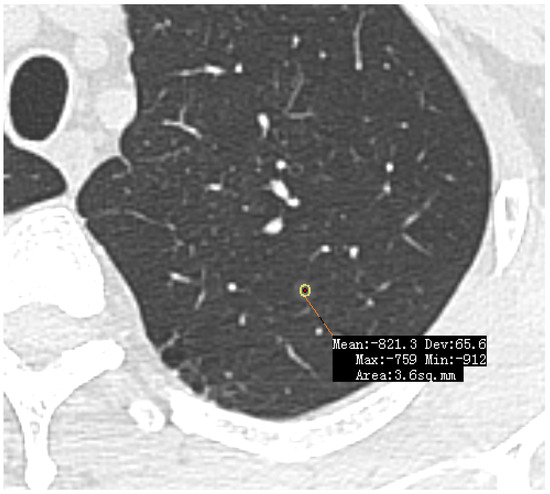

- Developments in low-dose CT screening;

- low-dose CT screening

- lung nodules